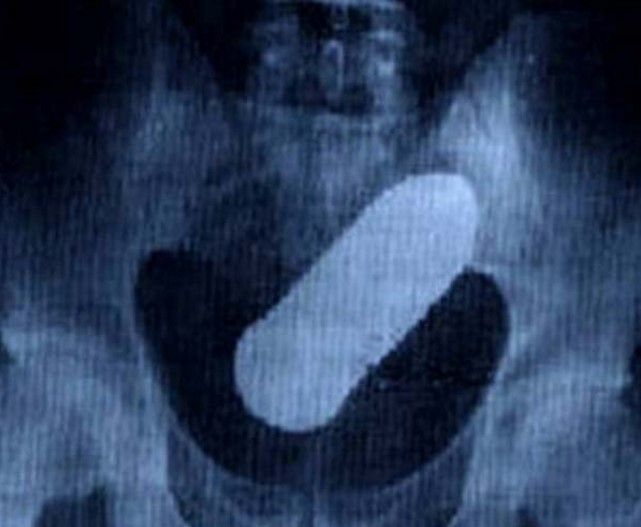

4. Timun ya?